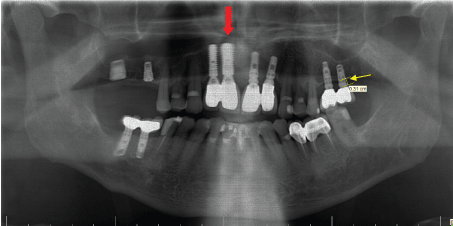

All implants were evaluated at 12 months after placement. During clinical recalls at 3 months, and 12 months changes in gingival margins were recorded with in millimeters by Williams Probe (Hu Friedy, Chicago, IL, USA) and bone loss evaluated in standart digital panaromic radiography (Figure 1). As part of the general routines, patients were enrolled in an individually designed maintenance care program for professional cleaning and examinations if needed. The change in the level of crestal marginal bone level was measured on standardized digital panaromic radiographt (Figure 2). All panoramic images were taken using the same panoramic machine (Eastman Kodak® 8000; Rochester, NY) by the same technician, according to the manufacturer’s reference guide. All images were recorded as JPEG files.

Figure 2: Red arrows shows that immediate implants, white arrows indicate the conventional implants. Yellow arrows indicate the measurement points.

The upper corner of the coronal shoulder of the implant was used as reference point, and measurements from the reference point to the first bone contact of the implant were performed using a PC. An implant was accepted successful when (1) no sign of failure seemed in panoramic and periapical radiography, (2) no pain or symptoms of infection were present, (3) ≥ 2 mm bone loss, (4) gingival margin recession.